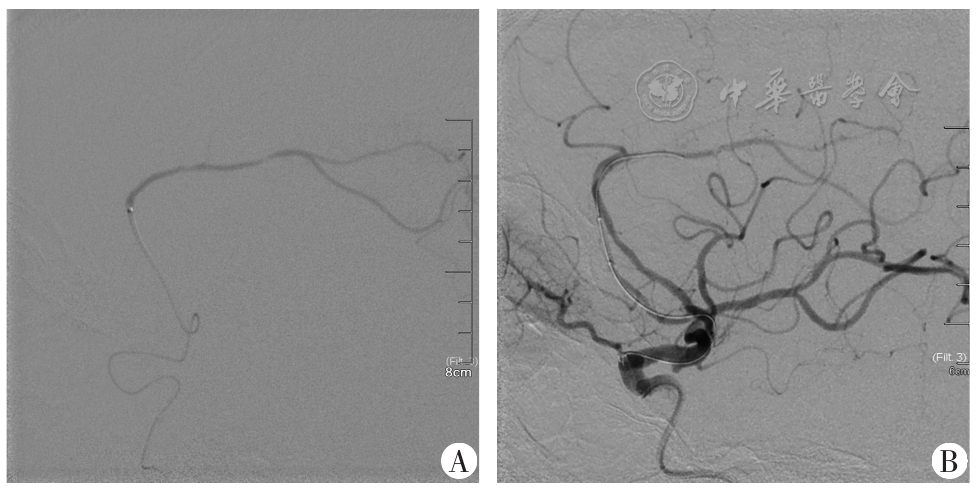

Stent retrieval thrombectomy and balloon angioplasty via the anterior communicating artery approach for acute anterior cerebral artery occlusion: one case report